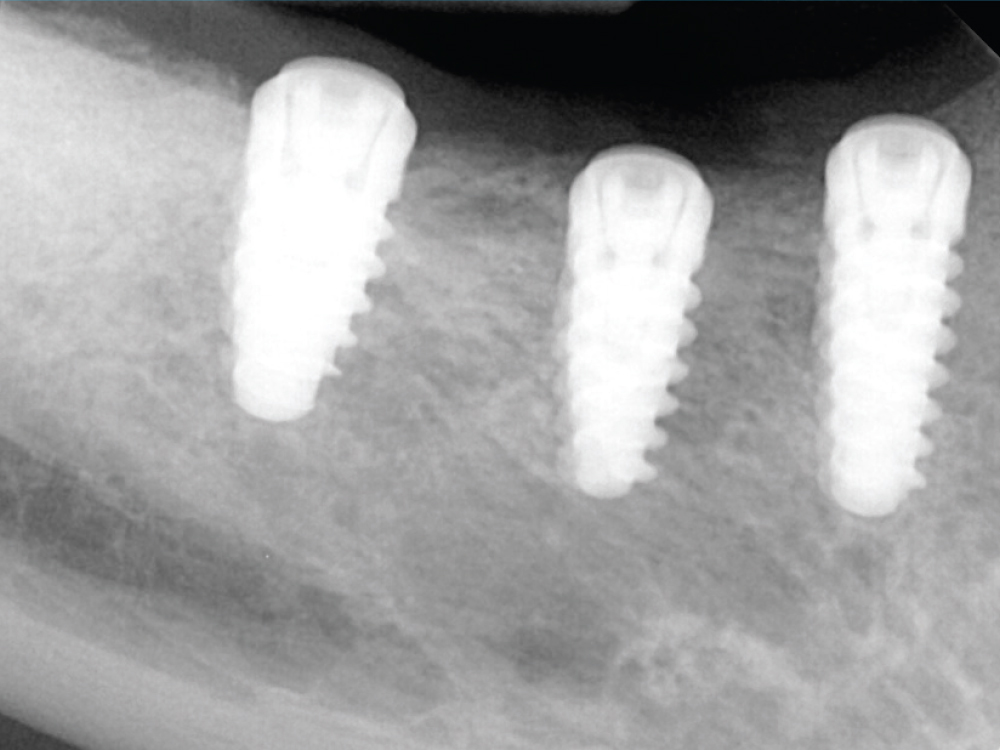

JN: Everything went very smoothly. This was a patient who had a lower 3-unit bridge on her right side that had failed a few years prior after the premolar root fractured and the second molar developed caries. These were previously endodontically treated teeth. I removed the teeth and grafted the extraction sockets for implant placement. On the left side of the patient’s mandible, she’d had an edentulous span in the posterior for quite a while and had never done anything about it because — and most dentists have heard this story before — she had one good side to chew on.

We took X-rays and CBCT scans, and there was plenty of bone to place the implants. I had a surgical guide made. I laid a flap, created the osteotomies and placed the implants through the guide. Everything went seamlessly and just as I expected. Ironically, the part that was surprising to me was that one of the implants got more stability than I was expecting. I started with her first two implants for the right side of the arch — where she’d had the 3-unit bridge fail — and placed them using the handpiece. Then I get to the site in the area of the most distal molar and the handpiece torqued out on me. This didn’t happen in the course, so I had to sit there and think for a second. The torque wrench goes up to the same Ncm, but then I remembered that there’s a straight wrench with no torque limit on it. So it was a slight pause in the surgery, but it was a great thing to happen because the primary stability I achieved was even better than what I could have expected. It was fantastic. Then I placed the two implants in the area of teeth #19 and #20, and that went perfectly.

For his first implant surgery, Dr. Nosti placed five Hahn implants in the posterior mandible for a patient who was especially eager to have him complete the entire process, from implant placement to the final screw-retained restorations.

JN: The integration, the healing process, and uncovering the implants and restoring them went extremely well. The bone levels were great. We worked with Glidewell and did BruxZir® Full-Strength screw-retained restorations on the patient’s right side and screw-retained IPS e.max® restorations on the left side. For both sides, we splinted the crowns to better distribute functional forces among the implants. The patient was extremely happy. The way the Misch Institute teaches you to handle patients medically has been very important in terms of maintaining patients’ comfort levels both during and after surgery. But of course, from the restorative aspect of it, this is nothing new to me and patients have been even happier with the outcome because I’m able provide them with the exact end result that I want and they expect because I’ve planned it from the beginning.